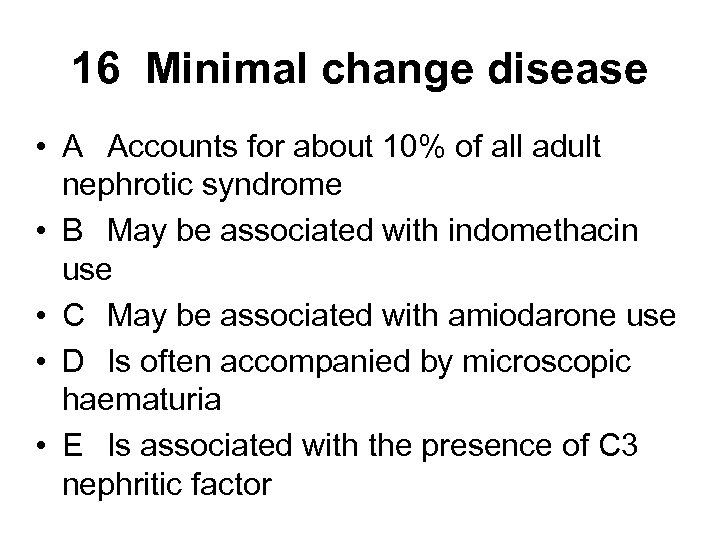

16 Minimal change disease • A Accounts for about 10% of all adult nephrotic syndrome • B May be associated with indomethacin use • C May be associated with amiodarone use • D Is often accompanied by microscopic haematuria • E Is associated with the presence of C 3 nephritic factor

16 Minimal change disease • A Accounts for about 10% of all adult nephrotic syndrome • B May be associated with indomethacin use • C May be associated with amiodarone use • D Is often accompanied by microscopic haematuria • E Is associated with the presence of C 3 nephritic factor

16 Minimal change disease • A Accounts for about 10% of all adult nephrotic syndrome • B May be associated with indomethacin use • C May be associated with amiodarone use • D Is often accompanied by microscopic haematuria • E Is associated with the presence of C 3 nephritic factor

16 Minimal change disease • A Accounts for about 10% of all adult nephrotic syndrome • B May be associated with indomethacin use • C May be associated with amiodarone use • D Is often accompanied by microscopic haematuria • E Is associated with the presence of C 3 nephritic factor